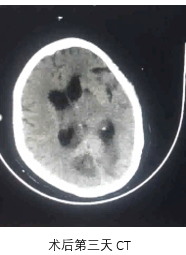

手术评估

病历夹什么径技·第151期|串联营病历夹:京广连营_https://www.jmylbn.com_新闻资讯_第78张

病历夹什么径技·第151期|串联营病历夹:京广连营_https://www.jmylbn.com_新闻资讯_第79张

病历夹什么径技·第151期|串联营病历夹:京广连营_https://www.jmylbn.com_新闻资讯_第80张

<<滑动查看下一张图片>>

• 患者术后转入重症医学科,症状一直未有改善,昏迷状,术后第5天家属放弃治疗自动出院。